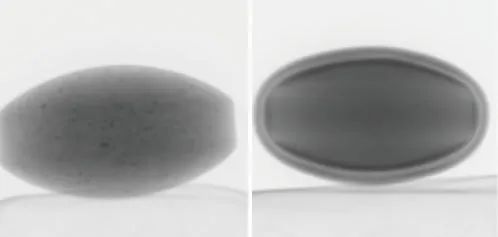

圖2 樣品照片:左邊片劑A,右邊片劑B

在本例中,觀察到兩種具有不同結構的片劑(片劑A和B)(圖2)。片劑的透視圖像如圖3所示。

片劑A (左) 片劑B(右)

圖3 片劑透視圖